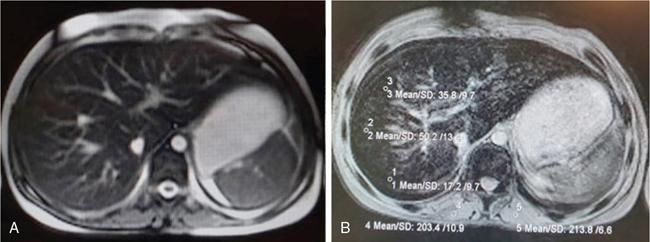

DIFFUSE PARENCHYMAL DISEASES OF THE LIVER Ishan Kumar, Ashish Verma The hepatic parenchyma is the site for multiple essential, interrelated, and complex metabolic activities to assimilate nutrients, detoxify the body, and synthesize vital molecules such as enzymes, hormones, cofactors and essential components of the coagulation pathway. The chemical reactions involved in each of these activities pose a threat to the hepatocytes, which may be damaged leading to the initiation of reparative processes. Further, the liver, being a highly vascular organ with multiple metabolic activities, is liable to be involved in many systemic vascular and metabolic disorders. On one hand, such changes cause healing of the tissue injury, but on the other hand, lead to diffuse parenchymal changes, which may result in suboptimal functioning of the organ. Such a condition is labelled as ‘diffuse liver disease’ and includes (a) diseases caused due to storage of certain chemical products of such chemical reactions labelled as ‘storage disorders’, (b) diseases caused due to reduction of blood flow to the organ, (c) parenchymal injury due to stasis of bile at various levels in the pathway due to varied causes, and (d) involvement of liver in systemic or organ-based inflammatory disorders. The mainstay of diagnosis of diffuse liver diseases is the detection of alterations in the biochemical parameters in blood indicative of liver function, which however is nonspecific to various aetiologies. The diffuse liver diseases in children are quite different from those in the adult population and constitute mainly of congenital or inherited metabolic and vascular diseases as opposed to diseases of acquired aetiologies in the latter population. The gross and microscopic pathological changes are accordingly different in the paediatric population and may be utilized to add specificity to the biochemical indicators as far as aetiological diagnosis is concerned. The invasive and potentially hazardous sampling mandated for histological evaluation of liver parenchyma has been replaced by an array of imaging modalities in recent times. The present chapter presents a review of the currently available imaging modalities (viz. cross-sectional imaging modalities such as ultrasonography, computed tomography [CT] and magnetic resonance [MR] imaging) for evaluation of diffuse liver diseases along with the pertinent imaging features and guidelines for their rational use in various indications. Also a short review of certain key technical and technological details is included. Jaundice and hepatomegaly are the most common clinical manifestations of liver disease. Anorexia is a nonspecific sign, often present in acute or chronic liver disease. Jaundice is a sign of increased bilirubin content in the blood, that can exist in four forms: (i) unconjugated bilirubin bound to albumin, (ii) unbound unconjugated bilirubin, (iii) conjugated bilirubin and (iv) δ fraction. Direct fraction includes both conjugated bilirubin and δ bilirubin. Conjugated hyperbilirubinemia is due to decreased excretion by liver or biliary tract obstruction. Pruritus, spider angioma on face and neck, ascites, portal hypertension, botchy palmer erythema, subcutaneous xanthoma, gastrointestinal (GI) variceal bleed, encephalopathy, renal dysfunction and pulmonary involvement are manifestations of advanced cirrhosis. Evaluation of total serum bilirubin and its fractional analysis into indirect (unconjugated) and direct (conjugated and δ fraction) bilirubin helps to distinguish between elevation caused by haemolysis and that due to hepatic dysfunction or biliary obstruction. Elevations in alkaline phosphatase (ALP), 5′ nucleotidase, and γ-glutamyl transpeptidase (GGT) levels are an indicator of biliary obstruction. However, it should be noted that normal growing children have significant elevations of serum ALP activity. AST (aspartate aminotransferase) and ALT (alanine aminotransferase) are significantly raised in acute hepatitis. ALT rise disproportionate to AST rise is seen in viral hepatitis. A predominant rise in AST is seen in echovirus infection, various metabolic diseases or alcohol-induced hepatitis. These aminotransferases are also elevated in NAFLD/NASH. ALT/AST rise is less marked in chronic liver disease. PT-INR, serum albumin levels can evaluate the hepatic synthesis function. Hypoalbuminemia suggests a bad prognosis. γ-Globulin is elevated in autoimmune hepatitis (AIH). Alpha-fetoprotein is raised in hereditary tyrosinemia or hepatic neoplasms. Indications of liver biopsy in the paediatric age group include neonatal cholestasis, metabolic liver disease, NAFLD, congenital hepatic fibrosis, abnormal biochemical liver tests of unknown aetiology, intestinal failure associated liver disease, acute liver failure and liver tumours. Although biopsy of children and infants is considered a safe procedure, due to incidences of shock, the North American Society for Pediatric Gastroenterology and Nutrition (NASPGHAN) has recommended liver biopsy in children not to be necessarily performed as outpatient procedures. Sonography-guided percutaneous liver biopsy has been reported to be safer, more efficient, more comfortable and only marginally more expensive than blind biopsy. The use of coaxial technique, determination of the number of passes and use of track embolization were at the discretion of the interventional radiologists. In cases of uncorrected PT-INR elevation, transjugular liver biopsy can be performed. Ultrasound (US) is a valuable tool in the diagnosis and management of diffuse liver diseases. It provides useful information about the size, surface, parenchymal architecture, biliary channels and blood flow of the liver. US examination of the liver is performed in the supine position with a convex (5–7.5 MHz) probe. High-frequency (7.5–12 MHz) linear transducers can be used in young infants because of their small size. US examination can be completed with the colour Doppler technique and US elastography, if needed. CT protocol typically requires image acquisition during the multiple phases with a slice thickness of 5 mm or less and a pitch ranging from 1 to 1.5. Contrast injected is 2 mL/kg through manual or mechanical injection. The arterial phase begins at 10–15 seconds and the portal phase is at 20–40 seconds after contrast injection. Equilibrium phase is obtained at 3 minutes, when needed. MRI protocol to evaluate paediatric liver chiefly includes free-breathing sequences, due to the challenge offered by an inadequate breath-hold in these patients. Due to the same reason, motion insensitive single-shot HASTE sequences or motion insensitive T1-weighted spoiled GRE single-shot sequences are also widely utilized in paediatric MR examinations. In slightly older children with a relatively uniform breathing pattern, external trigger signals from a breathing belt, or navigator techniques may be used to overcome motion artefacts from breathing. T1- and T2-weighted turbo spin-echo (TSE) sequences and T2-weighted single-shot sequences in axial and coronal planes are initially acquired to evaluate the anatomy and screen for pathologies. This is followed by a gradient echo (GRE) images to examine vascular structures. Multiecho images with T1-weighting can be acquired to evaluate the fat content of lesions. Contrast-enhanced MRI with intravenous injection of gadolinium (Gd)-based contrast agent is performed as routine in cases with suspected portal hypertension or in any associated suspected neoplastic lesion. This is usually clubbed with MRA for vascular mapping. Arterial phase and portal phase should be acquired 10–15 seconds and 20–30 seconds, respectively after the start of contrast agent injection. GRE T1-weighted sequence should be repeated continuously four or five times to include achieve all phases of liver perfusion. Finally, steady-state imaging should be performed in the equilibrium phase (3 minutes) using T1-weighted and T1-weighted fat-suppressed imaging sequences. MRI contrast media should be administered with caution after evaluation of eGFR, and is safer than the iodinated contrast media needed for CT scan examination, and is hence preferred. Liver size measurement is commonly obtained in one of the two ways (a) an anterior to the posterior measurement of the liver in the midclavicular line, (b) a dome-to-tip longitudinal measurement of the liver in the midclavicular line. Table 9.8.1.1 provides suggested upper limit values of liver and spleen length for various paediatric age groups. Despite advances in 3D US, volume measurements of liver size have not been incorporated in the routine clinical practice because it is time-consuming, requires considerable skill and technically difficult fusion of multiple 3D sweeps. Nonalcoholic fatty liver disease (NAFLD) is referred to as triglyceride accumulation in hepatocytes and encompasses a broad range of clinicopathological entities ranging from simple steatosis, steatohepatitis to cirrhosis. Its worldwide reported prevalence is approximately 2.6%–10% in the general paediatric population and as high as 38% of obese children under the age of 19 years. In India, the reported prevalence is as high as up to 22% in the general paediatric population and up to 45% in obese and overweight children. Hepatic steatosis currently is the most common cause of chronic liver disease in paediatric patients. Table 9.8.1.2 highlights the causes of hepatic steatosis in paediatric age group. The pattern of injury is similar to alcoholic liver disease. Nonalcoholic steatohepatitis (NASH) constitutes a subset of NAFLD, ranging from simple steatosis to inflammation and fibrosis. NASH in children has two distinct histological subtypes. Type 1 NASH resembles adult subtype with macrovesicular steatosis, lobular inflammation, and ballooning degeneration and perisinusoidal fibrosis. Type 2 NASH shows steatosis with portal fibrosis and is present in younger children with increased severity of obesity. ALT can be normal in 20% of the patient with NAFLD and liver biopsy is the gold standard for diagnosis as well as a semiquantitative assessment of disease severity. In clinical practice, the diagnosis and monitoring of NAFLD largely rely on ultrasonography. Grade I fatty liver refers to diffusely hyperechoic parenchyma with a well-visualized diaphragm (Fig 9.8.1). Bright liver with loss of periportal echogenicity and indistinctly visualized vessels is referred to as grade II and blurring of the diaphragm is classified as grade III fatty liver. Limitations of the US are lack of objective quantification and diminished sensitivity in cases where biopsy-proven steatosis ratio is less than 30%. Moreover, hepatic fibrosis and inflammation in cases of NASH are sonographically indistinguishable from simple steatosis. Contrast-enhanced US can diagnose the presence of fibrosis in NAFLD, which is evident from the decreased accumulation of microbubbles in the liver parenchyma. The distinction between hepatic steatosis and fibrosis is important clinically, as fibrosis can progress to cirrhosis if left untreated. US elastography has emerged as a promising technique to screen the children with NAFLD to look for ongoing steatohepatitis/fibrosis. Transient elastography is the most popular elastography technique which has shown excellent accuracy in the adult population with chronic hepatitis. However, its accuracy in NAFLD is significantly lower and the data of effectiveness in the paediatric population is limited. Acoustic radiation force impulse imaging (ARFI) has been shown to have a good correlation with AST/ALT ratios in obese children with NAFLD. An ARFI elastography value of >1.19 m/s predicts NASH-related hepatic changes in these patients while a value >1.75 m/s is suggestive of cirrhosis. Another study on shear-wave elastography has shown a high correlation in paediatric NAFLD patients with biopsy-proven hepatic fibrosis. A value of >5.1 kPa strongly predicts the presence of fibrosis whereas a value of >6.7 kPa is suggestive of stage ≥F2 fibrosis (Brunt scoring system). CT is a common modality utilized for assessment of hepatic pathologies, however is seldom used for assessment of NAFLD because of the risk of ionizing radiation. On noncontrast CT, liver attenuation <40 HU or hepatic attenuation 10 HU lesser than that of the spleen is considered as a sign of steatosis. Recent literature advocates the utilization of MRI in the evaluation of NAFLD. Fat imparts high signal intensity to the liver parenchyma on T1-weighted spin-echo MR images while it is mildly hyper- to hypointense on T2-weighted images. Conventional spin-echo imaging is relatively insensitive to mild-to-moderate fatty infiltration of the liver. The most commonly employed technique for detection of steatosis is chemical shift imaging (Dixon technique or dual-echo method) which utilizes two sets of gradient-echo images of the liver, that is in-phase and out-of-phase. On in-phase echo-time, water and fat signals add whereas, on out-of-phase echo-time, water and fat signals cancel each other. In nonfatty livers, the signal intensity of the liver parenchyma is unchanged between in- and opposed-phase images whereas a fatty liver shows a notable reduction of signal intensity on the opposed-phase images. Iron deposition in the liver can interfere with the assessment of steatosis. MR spectroscopy has been one of the most reliable techniques for the evaluation of hepatic steatosis (Fig 9.8.1.2). Protons in water molecules resonate at 4.7 ppm while that in triglyceride molecules resonate predominantly at 1.3 ppm. Other smaller lipid peaks can be obtained at 0.9, 2.0, 2.2 and 5.3 ppm. In a healthy nonfatty liver no triglyceride peak should be present. The presence of fat can allow measurement of area under water peak versus area under fat peaks to procure hepatic fat fraction. Proton density fat fraction (PDFF) measurement by MRI is another promising objective technique for quantification of steatosis in the paediatric patient. PDFF is the ratio of the density of mobile fat protons and the total density of protons including that from triglycerides and mobile water. Magnetic resonance elastography (MRE) is suggested as a noninvasive tool to evaluate liver stiffness that correlates with the degree of fibrosis. The technique is based on measuring the propagation of shear waves through liver parenchyma. A cut-off value for liver stiffness of 2.27 kPa has been suggested to predict Ludwig grade 2 or higher fibrosis. The technique depends on measuring the propagation of shear waves through the hepatic parenchymal fibrosis and differentiation of low-grade fibrosis from high-grade and also it may be feasible to distinguish steatosis from steatohepatitis. Success rate and accuracy of MRE is higher than US-based transient elastography. Cirrhosis is referred to as diffuse end-stage chronic liver disease characterized histologically by fibrosis and nodular regeneration, along with the disorganization of liver architecture. Although various underlying aetiology can lead to cirrhosis in children (Table 9.8.1.3), the most common causes in India are posthepatitic cirrhosis, Wilson’s disease (WD), AIH, biliary cirrhosis, biliary atresia and other metabolic diseases. In 5%–15% cases, the cause of cirrhosis may remain undetermined and is known as cryptogenic cirrhosis. Imaging is central to the diagnosis and management of children with cirrhosis (Fig 9.8.1.3). The role of imaging extends from diagnosis of cirrhosis to identification of complications and detection and characterization of nodules in cirrhotic liver. The imaging findings consist of changes in liver morphology, parenchyma and contour of the liver, vascular changes including portal hypertension, liver nodules and other complications of cirrhosis. Cirrhosis can lead to volume redistribution, which can be evaluated using either the US, CT, or MRI. Signs of early cirrhosis are atrophy of the segment IV, evident on imaging by increased fat segment IV and portal vein and between segment IV and left lobe. Signs of advanced cirrhosis are atrophy of the right lobe and segment IV with compensatory hypertrophy of left lobe and caudate lobe and fatty expansion of GB fossa. In some patients, a sharp notch is seen in the posterior surface of the liver (segment VI/VII). Some aetiology of cirrhosis may have different patterns of volume redistribution such as atrophy of left lobe and posterior segments in primary sclerosing cholangitis, diffuse hypertrophy in primary biliary cirrhosis, and absence of caudate hypertrophy in WD. The US can detect changes in liver segmental volumes based on linear measurements. C/RL (caudate/right lobe) ratio >0.65 calculated by comparing the transverse length of caudate and right lobe at the portal bifurcation, is a sign of cirrhosis. CT/MRI-based segmental volumetric analysis can reflect the morphological changes more effectively. Liver parenchyma in children appears as isoechoic to hypoechoic compared to the renal cortex in the US. The neonatal liver may reveal a bright echotexture. Hyperechoic parenchyma is seen in the fatty liver or liver fibrosis. Cirrhosis is seen as coarse and heterogeneous parenchyma. The liver surface in normal children appears as a hyperechoic, straight and regular line. The liver surface with diffuse irregularity or nodular surface is present in cirrhosis. CT and MRI in frank cirrhosis can reveal heterogeneous parenchyma along with the irregular surface. Diagnosis of early cirrhosis and fibrosis cannot be reliably made by the US where parenchyma may appear within normal limits. Similarly, CT and conventional MR sequences are also insensitive in early cirrhosis although early fibrosis can be seen as T1 hypointense/T2 hyperintense areas on MR and may show subtle enhancement. These T2 hyperintensities can be present as perilobular bands, perivascular cuffing, bands surrounding regenerative nodules, patchy fibrotic areas, or diffuse reticulation (honeycomb pattern). The role of US elastography and MR elastography is increasing in paediatric liver diseases for the detection of fibrosis and early cirrhosis and has been discussed in the previous section. US examination should be complimented with Doppler of the portal vein and hepatic veins if US features are suspicious of cirrhotic or fibrotic changes. The diameter of the portal vein increases with age. The mean diameter of the portal vein is 3.5 mm in children <5 years, 6.3 mm in 6–12-year old children, and 7–11 mm in >12-year-old children. Portal vein diameter is increased in portal hypertension; however, no reliable age-dependent cut-off values exist for the PV diameter in the diagnosis of portal hypertension in paediatric patients. Peak portal vein velocity in the paediatric age group is usually above 20 cm/s in a nonfasting child (15 cm/s in term neonate) along with some respiratory undulation. Peak portal vein velocity <16 cm/s in the paediatric age group is suggestive of portal hypertension. In term neonates, the values are above 15 cm/s. An increase in pulsatility of the portal vein (PI < 0.5) suggests portal hypertension. Reversal of portal vein flow (hepatofugal flow), presence of periportal collaterals or portal cavernoma, umbilical vein recanalization and various other collaterals are other signs of portal hypertension. Hepatic veins should be evaluated to rule out Budd–Chiari syndrome. CT or MR portal venography can comprehensively assess the extent and anatomical location of portosystemic collateral vessels in children with liver cirrhosis. Four groups of collateral channels can be identified: (a) periportal collaterals and portal cavernoma, (b) collaterals draining into SVC, that is left gastric vein (coronary vein), short gastric vein, oesophageal and paraoesophageal collaterals, (c) collaterals draining into IVC such as paraumbilical vein and abdominal wall collaterals, splenorenal and gastrorenal collateral, (d) mesenteric, retroperitoneal and haemorrhoidal collaterals. Various nodules can be seen in the cirrhotic liver including regenerative nodules, dysplastic nodules and HCC. The US is not sensitive in identifying these nodules and high-frequency linear-array transducer can contribute to their detection. CT and preferably MR can be used to characterize these nodules. Table 9.8.1.4 summarizes the imaging findings of these nodules on CT and MRI. It should be noted that HCC is rare in young children although it has been reported in children younger than 5 years in progressive familial intrahepatic cholestasis (PFIC) and Byler disease, biliary atresia. Recognizing the need for paediatric-specific guidelines for standardized interpretation and reporting CT and MR, ACR – LI-RADS (Liver Imaging Reporting and Data System) committee has convened the Pediatric LI-RADS Working Group in 2017. Hepatorenal fibrocystic diseases (HRFCDs) are developmental abnormalities of the liver and portobiliary system with associated fibrocystic degeneration of the kidneys. HRFCDs belong to the larger group of disorders collectively referred to as ‘ciliopathies’ a term describing the group of disorders affecting primary cilia which are an organelle present within the cholangiocytes. The ciliopathies in the liver is manifested as ductal plate malformation. Ductal plate is the embryonic precursor of the intrahepatic bile ducts and their abnormal development leads to cyst formation and alteration in portal venous development. Two major disorders are included in these malformations: (i) congenital hepatic fibrosis (affecting small intrahepatic ducts) and (ii) Caroli’s disease (affecting larger ducts). A combination of the CHF and CD is known as Caroli’s syndrome. Liver function test results in DPM may remain normal or be only modestly elevated. Few of congenital cystic liver pathologies are not associated with ciliopathies, such as autosomal-dominant polycystic liver disease (ADPLD) and portal fibrosis associated with congenital disorder of glycosylation (CDG) type Ib. Tables 9.8.1.5 and 9.8.1.6 innumerate the renal diseases and syndromes associated with ciliopathies. Carbohydrate-deficient glycoprotein syndrome type 1b Renal–hepatic–pancreatic dysplasia Oral–facial–digital syndrome type I US is the first-line modality, which can detect the distinctive morphological features of CHF that includes left lobe (segments II and III) hypertrophy, normal or hypertrophies segment IV, and atrophied right lobe. Preservation of the volume of the left medial segment is a feature that distinguishes CHF from cirrhosis resulting from viral hepatitis. The US can also detect changes in parenchymal echotexture, presence of splenomegaly, and can identify the evidence of cystic disease in the kidneys. Portal hypertension is one of the common presenting features of CHF despite normal hepatic lobular architecture and normal hepatic function. Application of the Doppler technique can detect the features of portal hypertension and cavernomatous transformation of the portal vein which can be present in up to 50% of the cases of DPM. The portal vein shows abnormalities in its ramification pattern with numerous, hypoplastic branches which are closely spaced, referred to as ‘pollard willow’ pattern. Studies have also shown enlarged hepatic artery and regenerative nodules in the arterialized hepatic parenchyma. In cases of Caroli’s syndrome, the US can easily identify cystic lesions or dilated intrahepatic bile ducts and can detect the stones in the ducts. Intraductal bridging (echogenic septa) can be seen traversing the dilated biliary duct lumen. Occasionally, the US can identify small portal venous branches surrounded by dilated biliary duct. Because of the absence of risks of ionizing radiation, US is the modality of choice in these children for long-term follow-up. CT can comprehensively demonstrate the morphological changes of CHF. Segmental computer-aided volumetric analysis of the hepatic parenchyma can identify the volume distribution with higher accuracy compared to the US. CT can also detect the parenchymal changes with higher sensitivity than the US. CT in these patients shows heterogeneously enhancing liver parenchyma, volume changes, and complete vascular mapping of the abdomen in cases of portal hypertension, identifying the portosystemic collaterals. Periportal cuffing can be identified on CT, indicative of periportal fibrosis. In Caroli’s disease, CT shows segmental and noncontinuous, saccular or fusiform dilatation of intrahepatic biliary radicals with the central enhancing dot representing portal vein branches (Fig 9.8.1.4). CT can identify the communication of the cyst with IHBD, differentiating them from PCLD. CT can also better detect the complications of CD such as cholangitis abscesses and cholangiocarcinoma. Seven per cent of the patients of CD can develop cholangiocarcinoma. MRI and MRCP seem to be a sensitive method for revealing biliary and renal abnormalities associated with congenital hepatic fibrosis and CD, even when sonography findings are normal (Fig 9.8.1.5). The parenchymal changes and heterogeneous architecture along with periportal fibrosis can be demonstrated on T2-weighted images, revealing hyperintensity along the portal vein and its branches. Regenerative nodules can be identified on T2-weighted and contrast-enhanced MRI. MRCP can delineate the communication between the cystic lesions and the biliary tree in cases of CD. Contrast-enhanced MRI can aid in the detection of complicating malignancies which can have a wide range of radiological appearances such as focal hepatic mass, intraductal mass, or biliary stricture. Multiplanar capability of MRI can enable its utility for preoperative planning in the affected children obviating the need for invasive preoperative cholangiogram to demonstrate the anatomy of the biliary tree. The differential diagnosis of Caroli’s disease is ADPLD, Von Meyerberg complex, choledochal cyst, sclerosing cholangitis, recurrent pyogenic cholangitis and peribiliary cysts. PCLD is seen on imaging as more than 20 round and smooth cysts without any communication with the biliary tree. Biliary hamartoma (Von Meyerberg complex) are seen as multiple/unique round uniform small cysts measuring 1–3 mm located close to portal tracts. Recurrent pyogenic cholangitis presenting with intra- and extrahepatic biliary dilatation is the most difficult diagnosis to exclude on imaging, however, the presence of saccular dilatation favours the diagnosis of Caroli’s disease. It should be noted that up to 20% of the cases of Caroli’s disease may have associated extrahepatic bile duct dilatation mimicking choledochal cyst and Caroli’s disease may even coexist with choledochal cyst. The presence of diffuse fusiform dilatation of the extrahepatic duct with less than 3 cm diameter combined with the characteristic intrahepatic ductal findings may help differentiate patients with Caroli’s disease from patients with a choledochal cyst associated with intrahepatic biliary dilatation. Routinely 1–2 mg of iron is absorbed by the intestine in a healthy child. Iron is recycled by extravascular haemolysis in the liver to meet the required amount (25 mg) in the spleen and bone marrow through Kupffer cells. Excess iron is bound to ferritin and hemosiderin in the hepatocytes. Excess iron in the body may be deposited in the liver, spleen, lymph nodes, pancreas, kidneys, pituitary, myocardium and GI tract. Up to 10–20 mg of excess iron does not cause tissue damage, in which case the term haemosiderosis is applied. Functional and structural impairment of the tissues occurs if the iron load (50–60 g) exceeds the compensatory mechanisms. In these cases, the term hemochromatosis is applied. Primary hemochromatosis is a genetic disorder occurring through mutation in the HPE gene which causes increased absorption of iron through the intestine. The secondary nongenetic form is more common and is caused due to multiple blood transfusions (transfusional haemosiderosis) in haematological disorders such as myelodysplastic syndrome, aplastic anaemia, beta-thalassemia major (transfusion haemosiderosis). Prolonged and excessive iron deposition can lead to endocrine abnormality, cardiac failure and liver parenchymal disease. Liver biopsy was considered as a reference standard for the detection and quantification of iron overload in hepatic parenchyma. However, it is largely replaced by radiological techniques because of the invasive nature and small size of sampled tissue while doing a single-site biopsy. The US cannot detect the features of iron overload in the liver parenchyma; however, it can be useful in detecting the complications of iron overload such as cirrhosis, hepatocellular carcinoma (HCC) or features of portal hypertension. CT scan is also of limited utility in hemochromatosis. Attenuation of >65 HU (15–130) with low attenuation of hepatic vessels relative to liver parenchyma on noncontrast CT is suggestive of iron overload, however can also be seen in WD, glycogen storage disorder, long-term amiodarone administration. MRI is the primary radiological modality used for diagnosis of iron distribution, quantification and monitoring of treatment response in liver iron overload (Fig 9.8.1.6). Various MRI techniques have been devised for iron overload estimation. This technique compares the signal intensity of liver parenchyma with the signal intensity of paraspinal muscles, which are assumed to be unaffected by iron content. GRE sequences are obtained with TR of 120 ms, flip angle 200, and varying TE of 2, 4, 9, 14 and 20 ms. Three ROIs of 1–2 cm are drawn in liver parenchyma and one on each paraspinal muscles. Liver iron concentration can then be obtained using a free online calculator provided by the University of Renne. Images are obtained with TR 2500 ms, flip angle 900 and variable TE of 6, 9, 12, 15, 18 ms. The images can be used to draw automated ROI covering the right lobe of the liver (excluding vessels) in the largest area and a T2 map of the same images can be generated. The technique quantifies the T2 shortening due to proton exchange between bulk water and exchangeable protons in ferritin. T2* takes into account the contributions of the T2 (1/R2) effects and the microscopic inhomogeneities introduced in (B0) by the hemosiderin clusters. For T2* measurement single breath-hold multiecho GRE sequences with TR of 25 ms, flip angle of 20 degrees, TEs every 0.25 ms from 0.8 to 4.8 ms are obtained. R2 * (1/T2*) values can be generated with ROI drawn from a single midhepatic section by drawing an ROI following the boundaries of the liver and excluding hilar vessels. Liver iron concentration can be obtained using a formula: [Fe] = 0.202 + 0.0254 R2*. This technique detects the enhancement in the local magnetic field caused due to ferritin or hemosiderin using a 3D breath-hold multiecho GRE sequence with the use of chemical shift–encoded water/fat separation, T2*/R2* mapping, and B0 field mapping. A quantitative susceptibility map of the parenchyma is generated. A local relative susceptibility value (ΔB0) is obtained drawing ROI which is expressed in parts per million (ppm), related to local iron deposition. With the ongoing research, stress is being placed upon the multiparametric quantitative MR imaging protocol which includes MR elastography (for fibrosis), multiecho chemical shift–encoded GRE to measure proton-density fat fraction (for steatosis quantification) and R2* relaxometry (for iron overload estimation). Hepatic iron overload has been shown to predispose to the development of HCC in the younger age group. The detection of HCC in the setting of iron overload is less difficult on T2-weighted sequences because the presence of iron behaves like a nonspecific contrast medium, such as superparamagnetic iron oxide (SPIO). However, care should be taken while evaluating these lesions, which may appear like hepatic cyst or haemangioma. Any nodule detected in these patients should be evaluated and characterized by the use of intravenous gadolinium contrast. The liver processes various metabolic processes of the body and hence it can be affected by multiple inherited metabolic disorders. The affection of the liver in these disorders may be in the form of hepatomegaly, cholestasis, acute liver failure or hepatic encephalopathy. WD is an autosomal recessive disorder of copper metabolism, first described in 1912 by Samuel Kinnier Wilson. The primary defect is a genetic abnormality located at chromosome 13 and q14.3, coding for copper-transporting P-type ATPase. An average diet contains 3–5 mg copper, 40% of which is absorbed in the upper GI tract and which is almost completely excreted in bile. The genetic defect leads to abnormality in this excretory function that leads to copper accumulation in the liver and other organs and tissues including brain and cornea. Liver disease in WD can range from asymptomatic transaminasemia, acute or chronic hepatitis, fulminant hepatic failure, and cirrhosis. WD can be misdiagnosed as AIH because both can result in similar autoantibodies. Imaging findings of liver manifestations can be categorized into four groups: (i) morphological changes, (ii) parenchymal changes, (iii) perihepatic changes, (iii) other findings. On CT, copper deposition in the liver may present with increased attenuation of the hepatic parenchyma, however, associated hepatic steatosis can decrease the overall attenuation which is within normal limits in most of the patients. Contrast-enhanced CT can show hypodense as well as hyperdense nodules and surface irregularity. The disappearance of hyperdense nodules has been documented after penicillamine therapy. Various MRI features of liver disease in WD has been described in the literature that includes (a) T1 hyperintense/T2 hypointense nodules (2 mm to 1 cm), (b) T1 hypointense nodules, (c) multiple hyperintense septae leading to ‘honeycomb pattern’, (d) high-intensity septa, (e) absence of parenchymal changes on MR. 31P MR spectroscopy of the liver in WD can show elevated phosphomonoester (PME) resonance and reduced phosphodiester (PDE) resonance, which have been shown to normalize after penicillamine and vitamin K therapy. Gaucher disease (GD) results from a deficiency of lysosomal enzyme β-glucocerebrosidase leading to the accumulation of ‘Gaucher cells’ in various organs. Imaging can help in the detection and characterization of liver infiltration, hepatomegaly, fibrosis, cirrhosis, iron deposition and HCC, all of which are associated with GD. On imaging, hepatosplenomegaly is the hallmark of GD (Fig 9.8.1.7). Recent literature recommends the utilization of CT or MRI over the US for volumetric assessment of liver and spleen sizes in GD with the expression of liver volume as multiples of normal volume (MN). Weight-based formula is used for calculation of liver and spleen volumes: normal liver volume (mL) = 25 × weight (in kg) ; and normal spleen volume (mL) = 2 × weight (in kg). A target liver volume of 1–1.5 MN and a spleen volume of 2–8 is aimed by the therapeutic regimens. On MRI, low ADC of liver and spleen indicates greater infiltration and worse prognosis, with ADC values correlating with chitotriosidase levels. Fibrosis can be detected and quantified using US shear-wave elastography, MR elastography, and nonimaging–based transient elastography. Studies have indicated the presence of liver iron deposition in GD due to associated hyperferritinemia, which can be quantified using R2* relaxometry. Hepatic nodules can be identified on imaging on GD. Most commonly these nodules represent a focal accumulation of Gaucher cells and are known as ‘Gaucheroma’. These lesions are hyperechoic on the US, hypoattenuating on CT, T1 hypointense/T2 heterogeneous nodules on MRI. These lesions do not merit biopsy; however, care should be taken to identify the lesions suspicious for HCC, that is large, irregular, hypoechoic, hypervascular lesions, which mandate further evaluation by multiphasic contrast CT or MRI. Besides the liver, evaluation of abdominal imaging should attempt to detect changes in spleen and visualized bones. GD in the spleen can manifest with splenomegaly, fibrosis, nodules, subcapsular infarcts and splenic necrosis. Osseous features of GD are osteopenia, osteonecrosis, pathological vertebral fractures and Erlenmeyer flask deformity. These are a group of disorders caused by defects in metabolism or storage of glycogen which broadly present with hepatic, myopathic, cardiac or other manifestations. GSD type I (Von Girke disease) presents with hepatic involvement. The US in these patients shows hyperechoic liver parenchyma because of fatty replacement and glycogen deposition. CT shows variable attenuation because hepatic attenuation is increased by glycogen and decreased by steatosis. There is a well-known association with GSD and hepatic tumours such as adenoma, focal nodular hyperplasia and HCC (rare). Adenomas are the most common tumours in GSD which show variable echogenicity. These lesions may contain fat, haemorrhage, or rarely dystrophic calcifications. A fat component can be detected using chemical shift MRI. These lesions should be monitored serially and malignancy should be suspected in case of rapid growth. α1-Antitrypsin deficiency is a rare autosomal recessive disorder that can cause chronic severe paediatric liver disease. In infants, this disorder can have a presentation similar to biliary atresia or idiopathic neonatal hepatitis. Moreover, scintigraphy cannot distinguish between biliary atresia, because similar to atresia, it can show uptake by hepatocytes and absence of biliary excretion due to paucity of lobular biliary ducts. The US in the neonatal period can help distinguish between the two, as it shows normal gallbladder and hepatic parenchyma. Older children may show imaging evidence of hepatic fibrosis or cirrhosis. MR elastography in this disorder is accurate for identifying fibrosis with a cut-off value of >3 kPa predictive of fibrosis. Various systemic illnesses can present with liver disease. The table summarizes the hepatic manifestations of various systemic liver diseases. TABLE 9.8.1.7 Paediatric diffuse liver diseases though forming a small subset of overall morbidity in children pose a formidable challenge for diagnosis as most cases present at a relatively early age. Imaging in these cases aims to make an aetiological diagnosis and rule out any associated complications, as the initial diagnosis is usually established by the biochemical analysis of liver function. Screening sonography usually forms the initial screening modality with MRI being the next stop problem-solving modality. CT scan has taken a back seat in current practice due to radiation exposure and the need to inject iodinated contrast media, both of which can be obviated by MRI. The former modality however remains essential in case an interventional procedure to treat portal hypertension is contemplated or percutaneous sampling from areas difficult to access by sonography is to be done. With the availability of an array of imaging modalities, it remains essential for an imaging expert to be clear as far as the choice of modality and order of its usage during the course on management is involved so that the most optimum imaging protocol can be offered to the patient. PEDIATRIC BENIGN HEPATIC MASSES (INCLUDING INFECTIONS) Kushaljit Singh Sodhi, Anmol Bhatia, Akshay Kumar Saxena Liver neoplasms constitute around 2% of all neoplasms seen in the pediatric population, and around 6% of the total abdominal neoplasms. Only one-third of the liver tumours in children are benign, while two-thirds are malignant. Benign hepatic tumours in children include lesions which are specific to children like mesenchymal hamartomas and vascular tumours, and the lesions that are also seen in adult population, such as adenoma, focal nodular hyperplasia (FNH) and nodular regenerative hyperplasia (NRH). Further, benign hepatic lesions affecting children include a wide variety of infections of bacterial, fungal and parasitic origin. In the present chapter, we will be discussing about the benign hepatic tumours and hepatic infections commonly seen in the pediatric population. A wide variation has been reported in the use of terminology for the hepatic vascular malformations in literature. According to the standard nomenclature adopted by the International Society for the Study of Vascular Anomalies (ISSVA), liver vascular tumours in children are termed as liver hemangioma. Liver hemangiomas in children are classified as infantile and congenital. Infantile hemangiomas usually begin to grow after birth, continue to grow during the first year of life and enter an involuting phase between 1 and 7 years. These tumours are positive for glucose transporter-1 protein (Glut-1), a protein that facilitates the transport of glucose across erythrocyte cell membranes. On the other hand, congenital hemangiomas are fully developed at birth and are characterized by Glut-1 negativity. These are further subdivided into a rapidly involuting group and a noninvoluting group, with some overlap between these groups. Hemangioma is a model of the angiogenesis concept proposed by Folkman et al and its development is related to a combination of upregulation of factors that promote angiogenesis and downregulation of its inhibitors. Most of these tumours are diagnosed in the first year of life, with these being slightly more common in females. Most commonly, these present as an asymptomatic mass in abdomen; however, associated life-threatening presenting complications have also been reported. These include high-output cardiac failure as a result of large arteriovenous shunts or Kasabach–Merritt syndrome of coagulopathy, severe hypothyroidism and acute hemoperitoneum due to tumour rupture. Lesions can be focal, multifocal or diffuse. Multifocal lesions are usually small and homogenous in appearance, while larger lesions may show areas of hemorrhage, calcification, fibrosis and necrosis. The liver is grossly enlarged in diffuse disease, which may cause mass effect on surrounding organs and vessels. Multifocal lesions frequently are associated with multiple cutaneous infantile hemangiomas with a Glut-1 positive marker. Biopsy of these masses should be avoided as there is a risk of bleeding, and the diagnosis is made based on typical imaging features and involution at follow-up. Well-defined hypoechoic or hyperechoic lesion, which may show heterogenous echotexture because of central hemorrhage/necrosis. A variety of flow patterns may be seen on colour Doppler due to the presence of shunts which may be portosystemic, or arteriovenous shunts. The hepatic arteries and veins usually enlarged, with large feeding arteries and draining veins seen surrounding as well as within the lesions. The lesions are usually hypoattenuating to the liver parenchyma with speckled calcifications seen in up to 50% of cases. The enhancement pattern is similar to that of hemangioma in adults and shows intense peripheral nodular enhancement on arterial phase with progressive centripetal filling on venous and delayed phases. Small lesions usually show intense and uniform enhancement (Fig. 9.8.2.1). The lesions show hypointense signal on T1-weighted images (T1WI) and hyperintense signal on T2-weighted images (T2WI). The tumour shows internal vascular flow voids and centripetal enhancement (Fig. 9.8.2.2). Heterogeneous signal may be seen due to presence of hemorrhage, thrombosis and necrosis. Calcifications may be seen in about 16% of cases.

Iron deposition in the liver

1. Liver-to-muscle signal intensity ratio

2. T2 and R2 relaxometry and T2* and R2* relaxometry

3. Quantitative susceptibility mapping